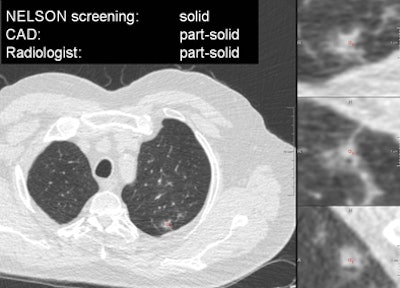

VIENNA - Taking a step beyond lung nodule detection schemes evaluated in previous studies, researchers from the Netherlands have developed an automated method of characterizing nodules as solid, part-solid, or nonsolid, pointing the way to different patient management paths, according to a presentation at ECR 2013.

In results from more than 100 patients who underwent lung cancer screening with CT as part of the Nederlands-Leuvens Longkanker Screenings Onderzoek (NELSON) lung cancer screening trial, researchers from Radboud University Nijmegen Medical Centre in the Netherlands and several other institutions showed that their automated computer-aided detection (CAD) scheme for characterizing nodule types according to Fleischner Society criteria was nearly as accurate as the findings of an expert thoracic radiologist -- who despite his experience, expressed his own doubts about his ability to classify nodules correctly in every case.

"Now we have guidelines for solid nodules, for subsolid nodules, and the guidelines for subsolid nodules also differentiate between part-solid and nonsolid nodules," Jacobs said. "Classifying nodules in these three categories is crucial for patient management. The purpose of this study was to develop a CAD tool to do this automatically ... and to compare the performance of our CAD tool to an experienced thoracic radiologist on a large dataset obtained from a screening database."

The experienced thoracic radiologist slightly outperformed the algorithm in all three categories; however, the radiologist clearly needed help -- saying that he was uncertain about his classification in 25% of the cases, Jacobs said.

"Nodule characterization is a difficult task, indicated by 25% of the cases in which an experienced radiologist was uncertain about his classifications, especially the differentiation between part-solid and nonsolid nodules. It's a difficult part, both for the CAD and the radiologist," Jacobs said. "And we did not yet assess the interobserver variability of the radiologist."